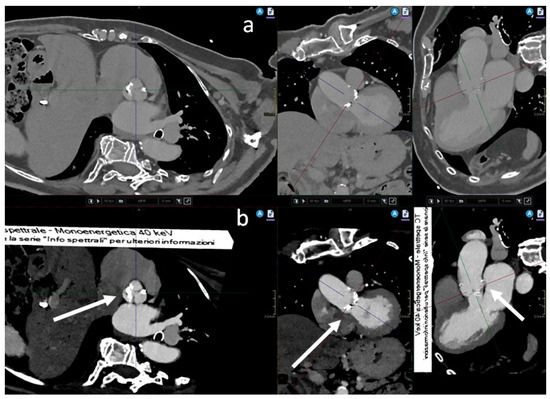

Transcatheter aortic valve implantation (TAVI) is a less invasive alternative to surgical implantation and its implementation is progressively increasing worldwide. We routinely perform pre-procedural aortic angiography CT to assess aortic dimensions and vascular anatomy. This study aims to evaluate the image quality of [...] Read more.

Transcatheter aortic valve implantation (TAVI) is a less invasive alternative to surgical implantation and its implementation is progressively increasing worldwide. We routinely perform pre-procedural aortic angiography CT to assess aortic dimensions and vascular anatomy. This study aims to evaluate the image quality of CTA for TAVI planning using dual-layer spectral CT, with virtual monoenergetic image reconstructions at 40 keV. Thirty-one patients underwent a CTA protocol with the injection of 20 mL of contrast media. Image quality was assessed by measuring the mean density in Hounsfield Units (HU), the signal-to-noise ratio, and the contrast-to-noise ratio in VMI reconstructions. Additionally, a blinded subjective analysis was conducted by two observers. The results showed significant enhancement at all sampled vascular levels with a gradual decrease in HU from proximal to distal regions. Favourable subjective ratings were given for all parameters, with greater variability in the evaluation of iliac axes. A significant negative correlation (p < 0.05) was observed between BMI and CA at all vascular levels, indicating reduced contrast enhancement with increasing BMI. Spectral CT, along with reducing iodine load, allows for obtaining high-quality images without a significant increase in noise. The reduction in iodine load can have positive implications in clinical practice, improving patient safety and resource efficiency. Full article

Show Figures

Graphical abstract